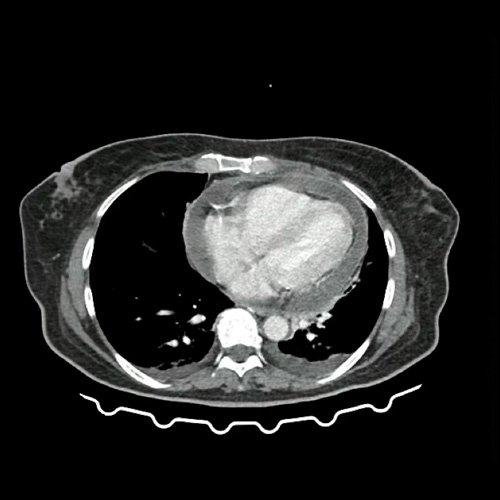

Anexo 4: Ecocardiograma transesofágico DÍA 12

Durante el DÍA 12, por inestabilidad hemodinámica en contexto de endocarditis infecciosa aguda de válvula tricúspide y pulmonar nativa asociado a derrame pericárdico severo, se decide su pase a unidad de terapia intensiva. Se le realiza ecocardiograma transesofágico, constatando las vegetaciones visualizadas previamente y presencia de un absceso en anillo tricuspídeo. Asimismo, se encuentra en discusión la conducta quirúrgica debido al elevado riesgo de la paciente, debiendo ser reevaluada por equipo de cirugía cardiovascular a los 7 días de la interconsulta (aproximadamente día 20 de internación).

Contextualizando a la paciente que tiene un derrame pericárdico sin impacto hemodinámico, asintomática, severo, agudo. En el estudio ecocardiográfico, inicialmente del día 2 hacia el día 9, cambia de características, siendo informado como marcadamente engrosado, con fibrina, impresiona contenido denso. Se realiza pericardiocentesis con material macroscópicamente purulento. A su vez, se visualizan múltiples vegetaciones en válvula tricúspide y pulmonar. Por lo que interpretamos que la paciente tiene el diagnóstico de una endocarditis infecciosa (EI).